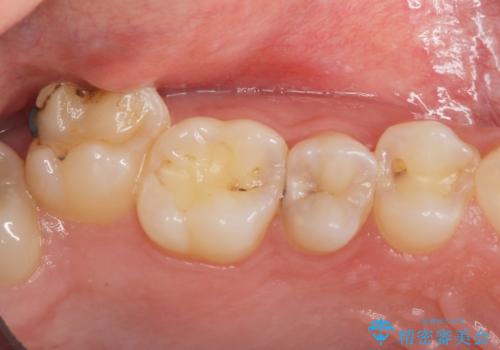

- 全体的にむし歯を治していきたいとのことで来院。

検査の結果、症状はないものの右上の奥歯に虫歯が見つかりました。

笑うと外からも見える位置であるため、白いセラミックでの治療となりました。